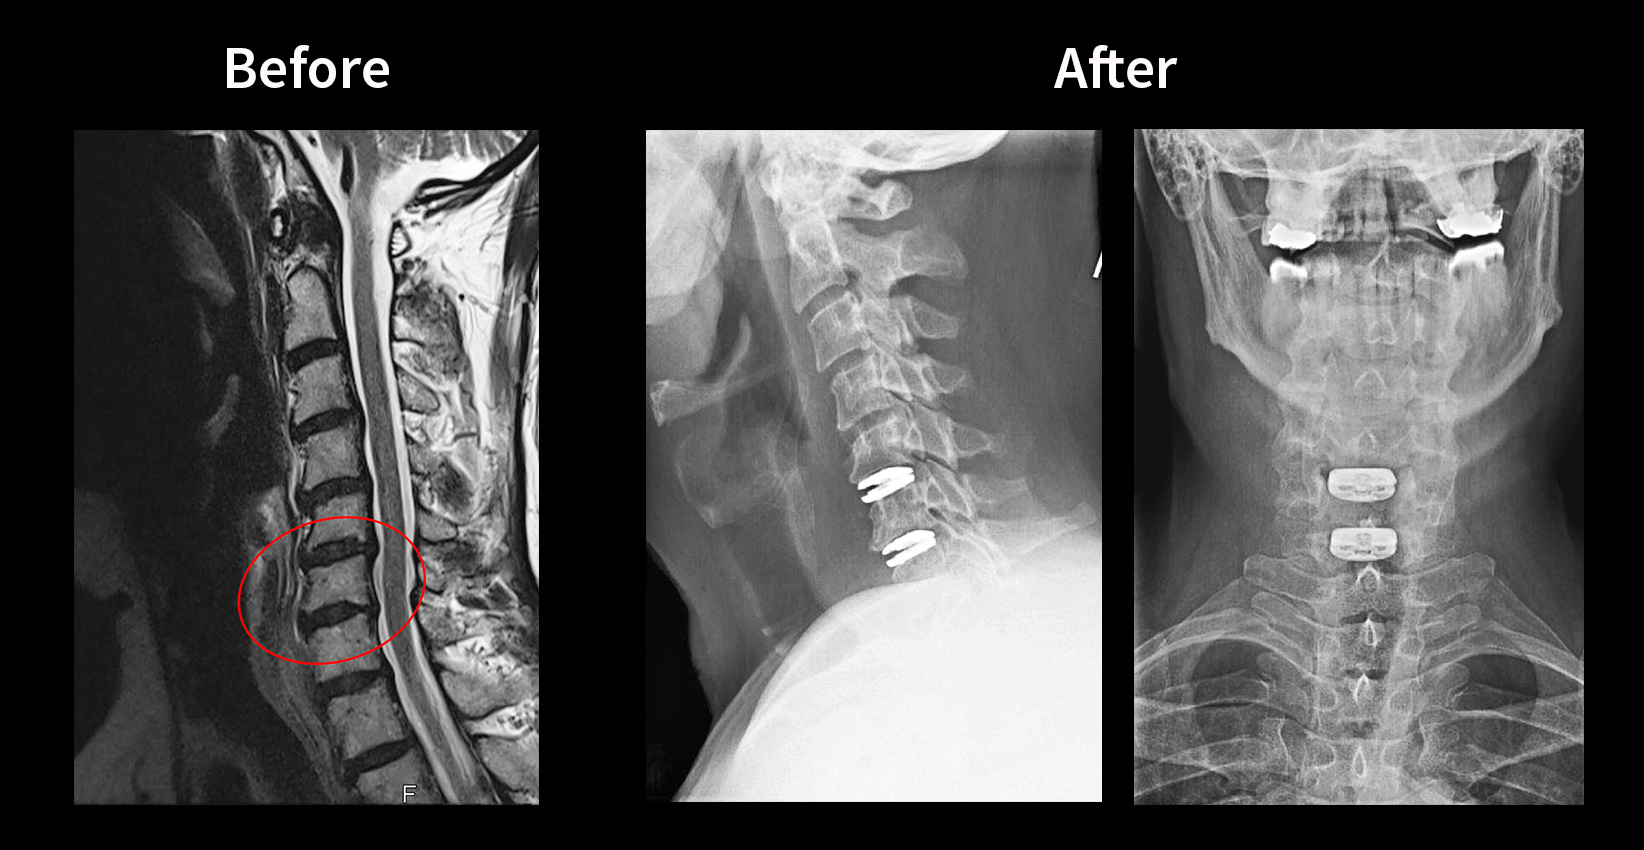

Cervical disc herniation occurs when the cushioning discs between the vertebrae in the neck region rupture or protrude beyond their normal boundaries, potentially compressing nearby nerves. This condition often results in discomfort, numbness, or pain radiating from the neck down through the shoulders and arms. Dr. Sylvain Desforges, a prominent figure in spinal care within Québec, brings more than 30 years of experience to the intricate evaluation of these spinal disorders. His comprehensive approach emphasizes a detailed patient evaluation, avoiding premature surgical diagnoses, and instead focusing on tailored, evidence-based treatment protocols.

Key to Dr. Desforges’ method is the insistence on scientific rigor and strict adherence to ethical standards, complying fully with Canadian and Quebec medical regulations. Through detailed assessments, he distinguishes the severity of disc displacement and nerve involvement, guiding patients through a path optimized for individual recovery potential. His clinic in Candiac focuses on integrating advanced technologies like dynamic spinal implants and laser therapy alongside osteopathic techniques to support natural healing and symptom relief.

- Neurovertebral decompression therapy designed to alleviate disc pressure without surgery

- Custom dynamic spinal implants in cases where conservative care isn’t sufficient

In Candiac, the incorporation of modern technologies significantly enhances the quality of care delivered to patients facing cervical disc herniation. Under the expert guidance of Dr. Desforges, therapies such as non-surgical spinal decompression, laser therapy, and dynamic spinal implants represent the frontier of conservative and minimally invasive care.

Non-surgical spinal decompression therapy utilizes mechanical traction devices designed to gently stretch the spine. This process relieves pressure on the affected discs, improving nutrient exchange and promoting tissue healing without the risks tied to surgery. Laser therapy complements this by targeting inflammation and stimulating cellular repair mechanisms, an approach well documented in leading clinical studies.

Dynamic spinal implants serve as an option for select cases where structural support of the spinal segment is necessary. These implants aim not only to stabilize but also to preserve motion, improving long-term spine function. Accessibility to such advanced interventions in Candiac through Dr. Desforges’ clinics offers patients options rarely available elsewhere in Canada.